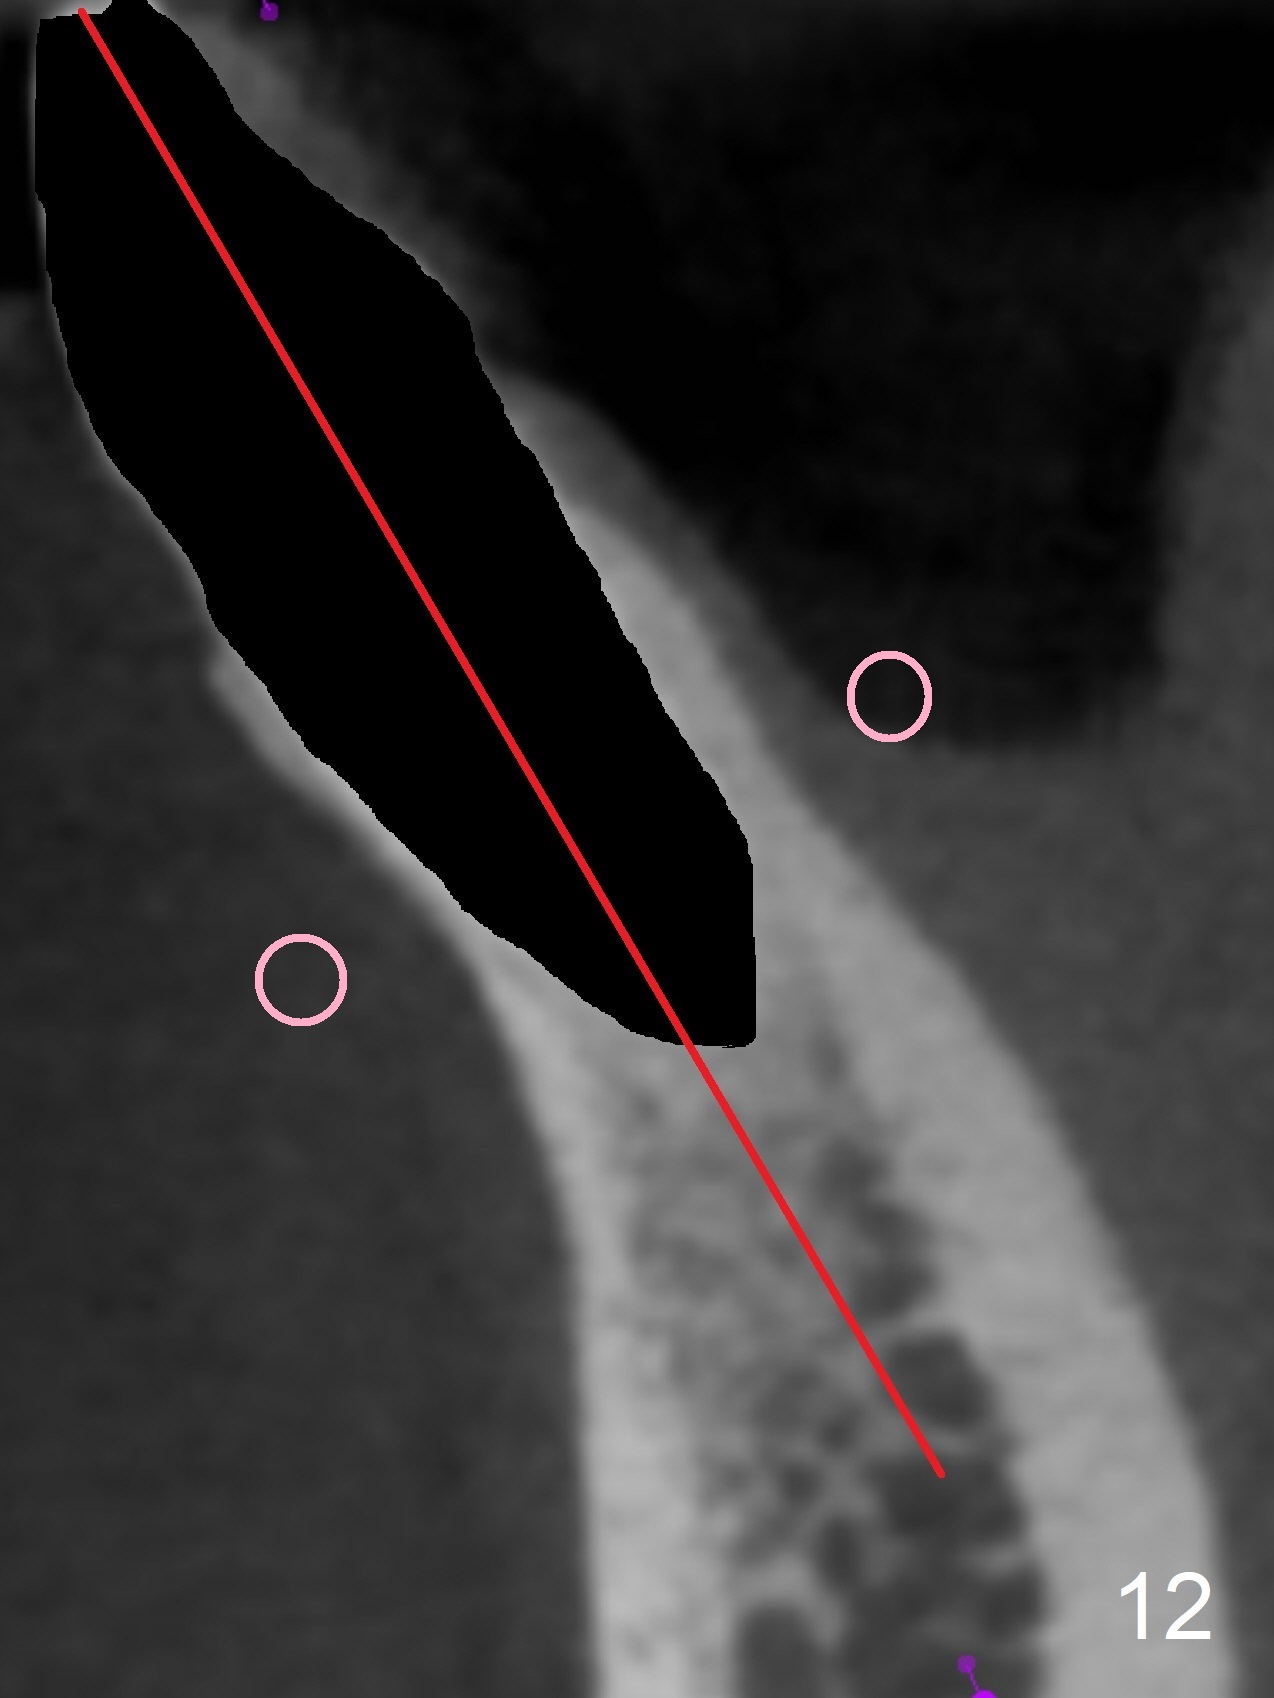

In fact the apex of the lateral incisor is also in the center of the alveolus (Fig.9 *). Osteotomy established in the lingual slope for a long distance (Fig.10,11) will perforate the lingual plate. The correct method of osteotomy is to set up in the middle of the socket and along the long axis of the alveolus with 2 fingers holding the alveolus (Fig.12 (2 circles)). The problem for this case is to use the lower RPD as a guide. With the RPD in place, the tactile sensation is lost.

After change in abutment at #27 and abutment height adjustment at #26 and 27 (Fig.13), splinted provisional is fabricated with clearance from the RPD (Fig.14) and seal of the sockets (Fig.15). Acute submandibular and submental cellulitis develops with sublingual purulent discharge 1 month 10 days postop (Fig.16). CT confirms lingual plate perforation at both sites (Fig.17,18; red line: original socket). With block anesthesia, removal of these implants causes mild discomfort. With Hydrogen Peroxide and normal saline copious irrigation, pain reduces when anesthesia subsides. Bone graft will be placed at the sites approximately in 2 weeks. In fact the infection is not controlled until 2 weeks later (Fig.19). The clasp has to be covered with acrylic for comfort (Fig.20). The previous implant sites heal 1.5 months post implant removal (Fig.22).